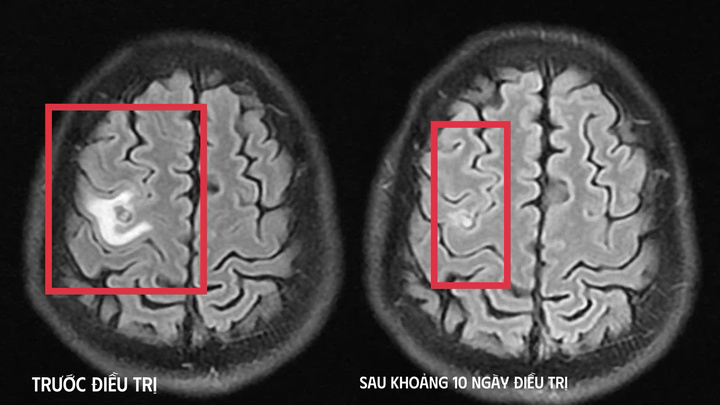

Người đàn ông 39 tuổi thể trạng khỏe mạnh bắt đầu co giật trước khi vào viện 8 ngày, ngỡ là u não đi khám mới biết có sán làm tổ.